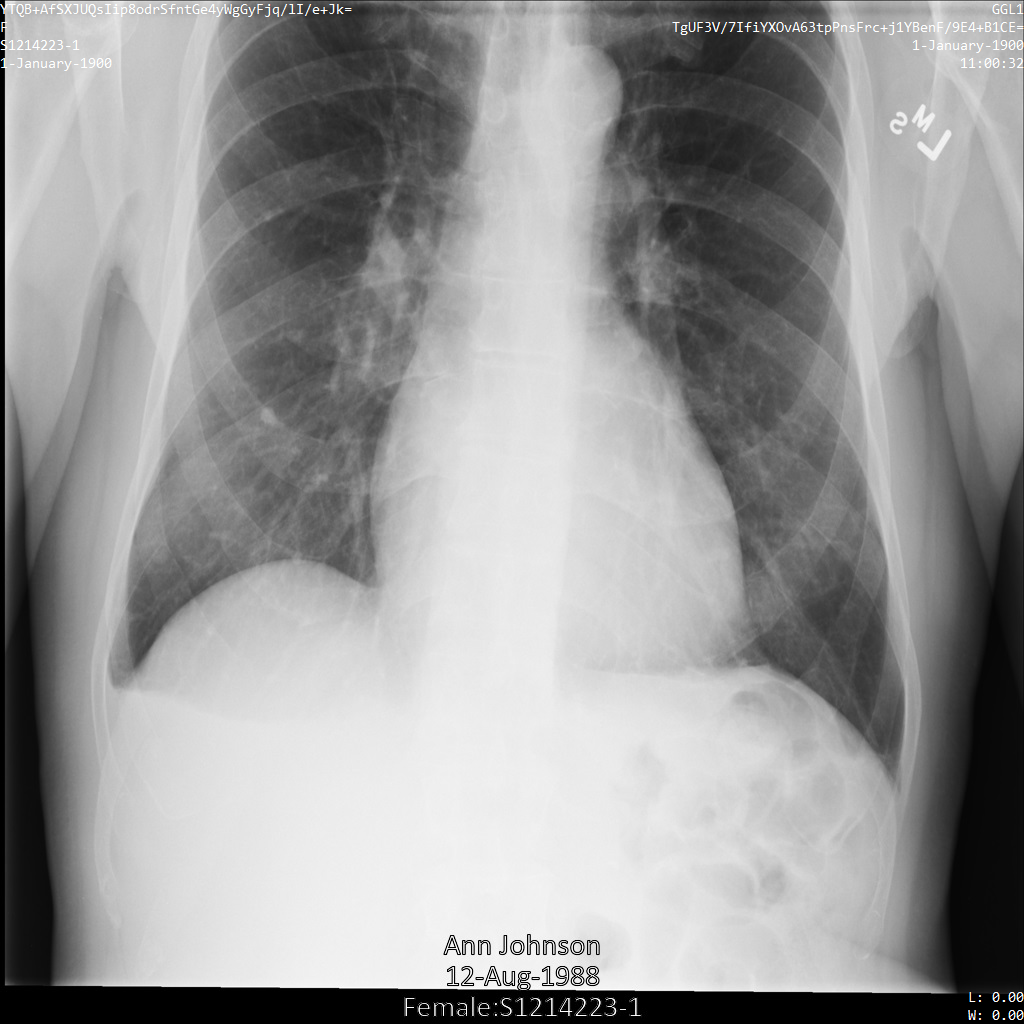

Nachdem Sie das Bild mit dem Tag-FilterprofilATTRIBUTE_CONFIDENTIALITY_BASIC_PROFILE an die Cloud Healthcare API gesendet haben, wird das Bild wie folgt angezeigt: Während die in den oberen Ecken des Bildes angezeigten Metadaten entfernt wurden, bleibt die eingebrannte PHI unten im Bild erhalten.

Informationen zum Entfernen des eingebrannten Texts finden Sie unter Eingebrannten Text aus Bildern entfernen.